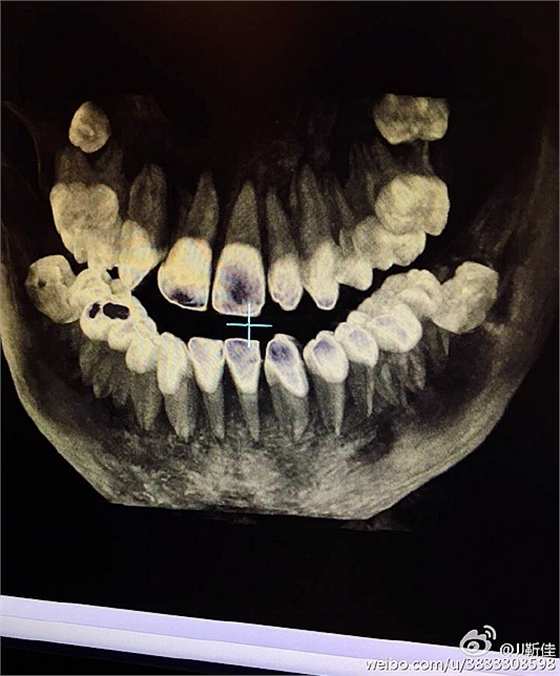

左下67缺失

ct定位

術后拍片